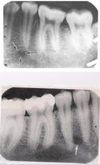

What structure is represented in the following picture?

Mandibular Canal

What radiolucent structure is represented in this picture?

Mental Foramen

What is the radiolucent structure represented in the following picture?

Inferior Border of the Mandible

What structure is represented in the following photo?

Genial Tubercles